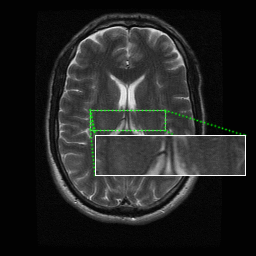

A software for automatically segmenting dissimilar regions in medical images acquired with magnetic resonance imaging, computed tomography or ultrasonography has been developed and implemented. The software can be used to highlight abnormal regions in medical images.

The algorithm operates in unsupervised mode hence does not require any parametrisation. This allows the physician to fully focus on the task of identifying diseased areas.

'The program has delineated the diseased area very clearly with a unique colour. The other part of the image with the same colour outside the diseased part of the image, can be differentiated by the physician as the non-diseased area as it is in the border of the uterus.

Looking at the original image only an expert sonologist will be able to pick up this abnormality. Therefore this program will be surely useful to differentiate in case of borderline pathology where the sonologist will not be very sure of the diseased area.

The separate region within the diseased area gives additional information that, that area has got the core of the disease, and it is spreading out from that location'

- comment from a sonologist